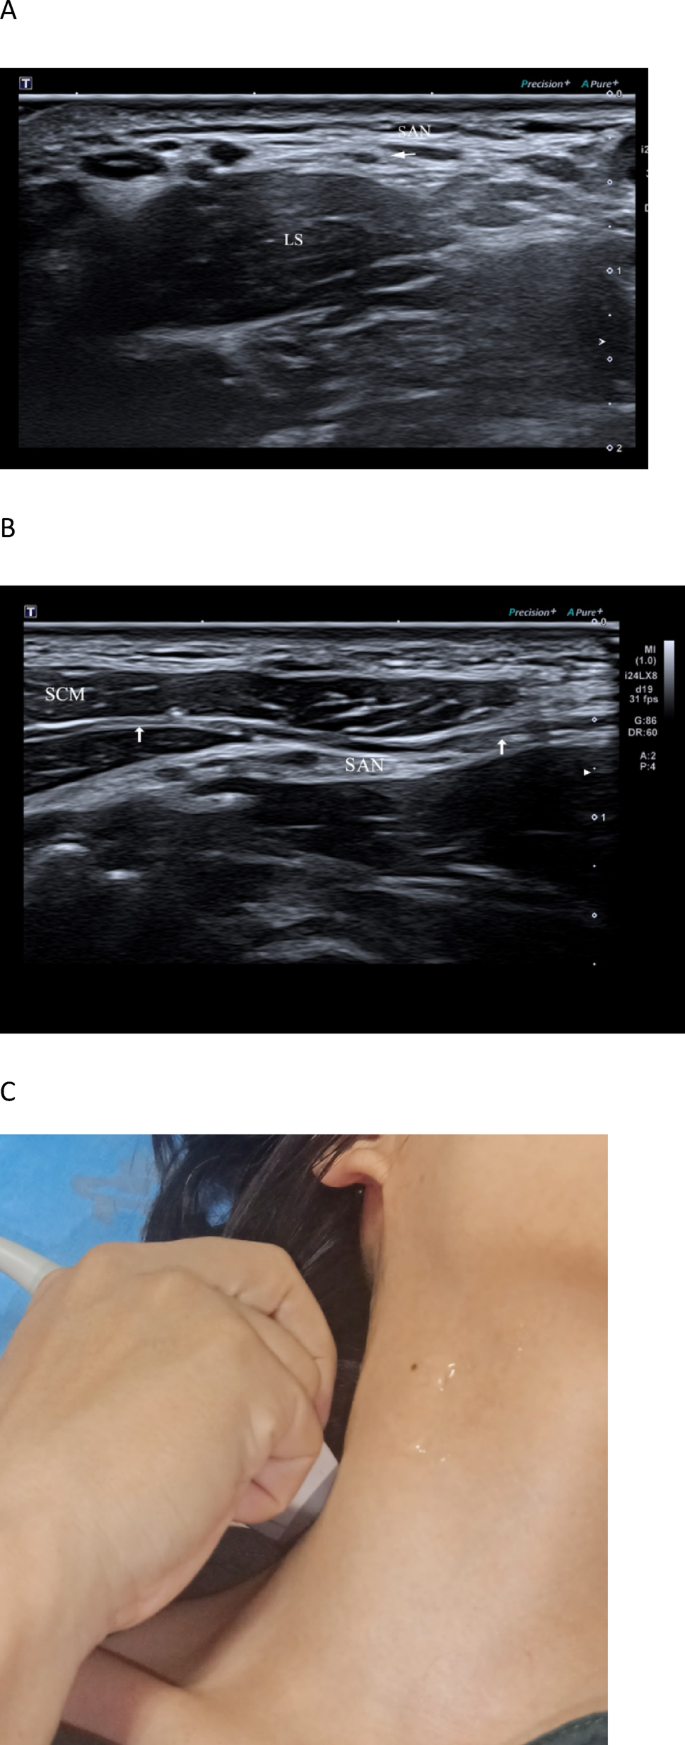

Identifying the spinal accessory nerve (SAN) at S2. A Short-axis and B long-axis ultrasonographic views show the SAN (arrows) coursing on the surface of the levator scapulae (LS) within the posterior cervical triangle; the adjacent sternocleidomastoid muscle (SCM) is shown for orientation. C Transducer placement for the short-axis view.